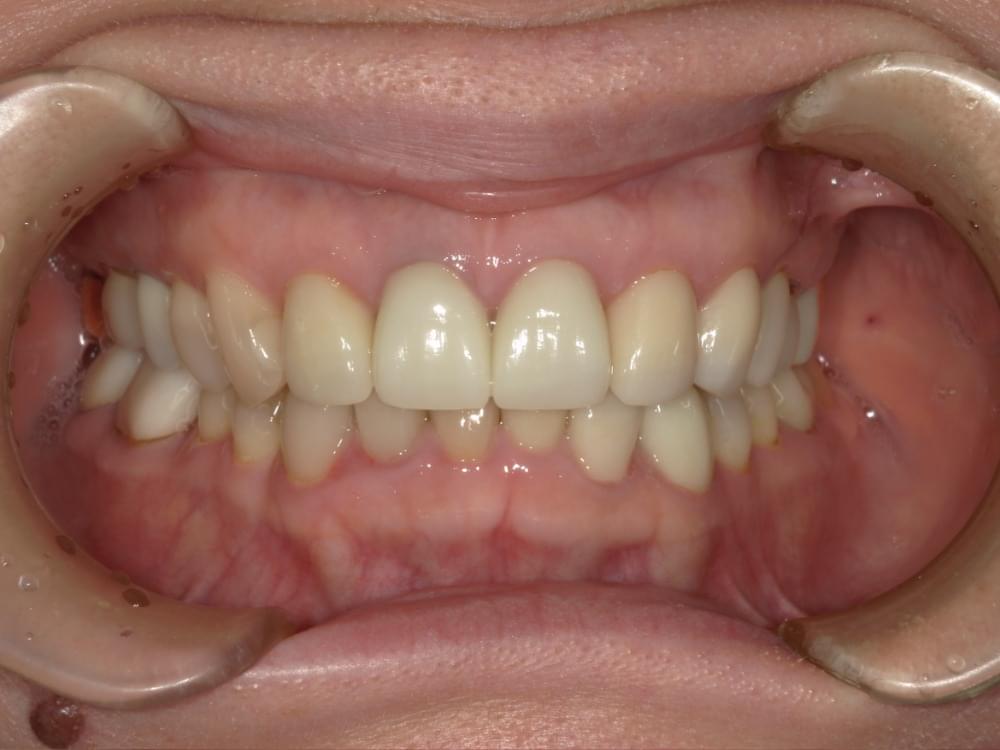

歯周病治療プログラムの治療例1

治療の概要

治療内容

行動科学に基づき、「自分の歯は自分で守る」という意識改革や行動変容を促しながら、スケーリングや歯ブラシ・フロス指導を行いました。

治療期間・回数・時間

1.5ヶ月・5回・計5時間

費用

29,500円+税

リスク・副作用

歯肉の痛み・出血